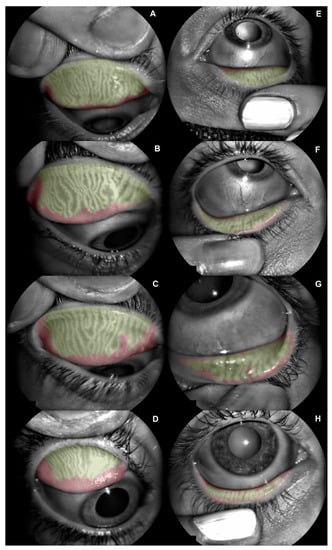

| Superior Eyelid MGD (Percentage) | 26.40 ± 12.98 (5.40 to 49.40) | 32.90 ± 5.42 (21.40 to 42.80) | 0.05 |

| Inferior Eyelid MGD (Percentage) | 36.50 ± 15.96 (10.90 to 76.60) | 31.61 ± 8.68 (19.30 to 45.40) | 0.25 |

| Lipid Layer Thickness (Guillon Pattern) | 1.64 ± 1.05 (0.00 to 4.00) | 1.35 ± 0.81 (0.00 to 3.00) | 0.39 | |

| Lipid Layer Thickness (Guillon Pattern) | 1.52 ± 0.61 (0.00 to 2.00) | 1.38 ± 0.65 (0.00 to 2.00) | 0.38 | |